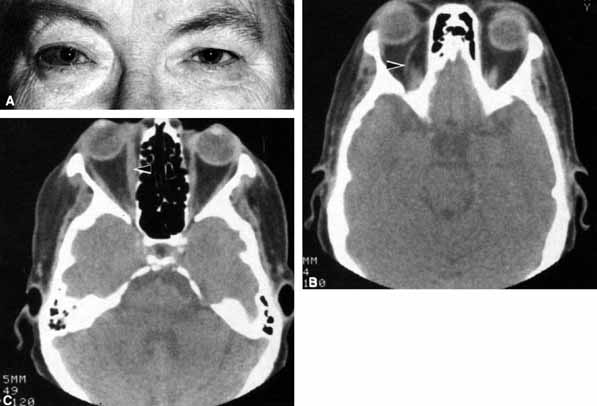

A 70-year-old woman presented with a 6-month history of progressive diplopia and ptosis. She demonstrated complete right third, fourth, and sixth cranial nerve palsies, and hypesthesia of cranial nerve V1 (Fig. 22A). The right pupil was dilated. Computed tomography (CT) disclosed an intracavernous aneurysm (see Fig. 22B).

Fig. 22 A. A 70-year-old woman with complete right third, fourth, and sixth cranial nerve palsies. Hypesthesia of cranial nerve V1 was also present. B. CT scan demonstrates an intracavernous aneurysm (arrow).

The so-called superior orbital fissure syndrome occurs when an infiltrative, inflammatory, or ischemic event occurs within the superior orbital fissure, but not in the orbital apex.4 A complete superior orbital fissure syndrome occurs when all the neurovascular components passing through the superior orbital fissure are damaged, producing a total ophthalmoplegia, ptosis, and anesthesia of cranial nerve V1 (see Fig. 22A). The pupil may be dilated, miotic, or midposition and fixed, depending on the balance of parasympathetic and sympathetic damage. The superior ophthalmic vein, best seen on CT, may be dilated if venous outflow from the orbit is obstructed. Clues to venous outflow obstruction are increased intraocular pressure, fullness of the upper eyelid, and hyperemia of the deep Tenon's vessels. Ophthalmoscopically, the retinal veins may be dilated. The effect of a lesion in the superior orbital fissure or the anterior cavernous sinus cannot be differentiated clinically (see Fig. 22B). When the posterior cavernous sinus becomes involved, hypesthesia of cranial nerve V2 may also be present.

The only difference between a superior orbital fissure syndrome and an orbital apex syndrome is the presence of visual loss caused by optic nerve involvement. Visual acuity, color vision, or the visual field are abnormal. An ipsilateral relative afferent pupil defect is present.